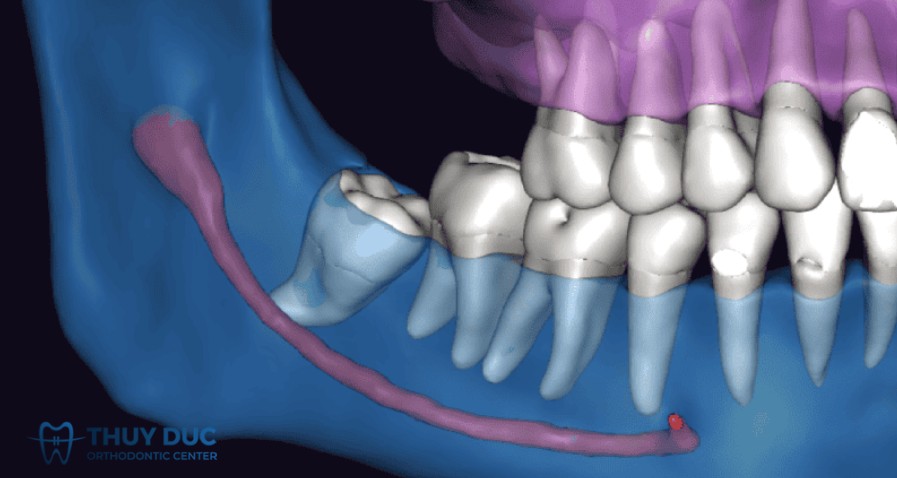

Tổn thương dây thần kinh

Một trong những biến chứng nghiêm trọng nhất khi nhổ răng khôn hàm dưới là tổn thương dây thần kinh, đặc biệt là dây thần kinh răng dưới (Inferior alveolar nerve – IAN) và dây thần kinh lưỡi (Lingual nerve – LN).

Hậu quả có thể xảy đến với bệnh nhân là tình trạng tê môi – cằm, dị cảm (ngứa râm ran, mất cảm giác), khả năng hồi phục tùy thuộc mức độ tổn thương; tổn thương nhẹ có thể hồi phục vài tuần đến vài tháng, nhưng nếu nặng (như cắt ngang dây thần kinh) có thể dẫn tới mất cảm giác vĩnh viễn.

Trong một nghiên cứu tại tại Oman với 1.116 răng khôn được nhổ, tổn thương dây thần kinh chiếm 7,2% trường hợp, trong đó phần lớn là tạm thời; tổn thương vĩnh viễn chiếm khoảng 0,7% ở răng khôn hàm dưới (LN ~0,5%, IAN ~0,2%).

Một nghiên cứu tổng quan khác ghi nhận: dây thần kinh răng khôn hàm dưới bị tổn thương với tỉ lệ khoảng 0,35% và LN khoảng 0,69% trong nhổ răng khôn hàm dưới.

Vì vậy, khi có quyết định nhổ răng khôn, bệnh nhân nên tìm hiểu các phòng khám uy tín để bác sĩ đánh giá kỹ bằng phim (ví dụ CT/CBCT) để xác định mối quan hệ giữa chân răng khôn và ống thần kinh, và cân nhắc phương án giảm thiểu rủi ro (ví dụ giữ lại chân răng – coronectomy) nếu cần.